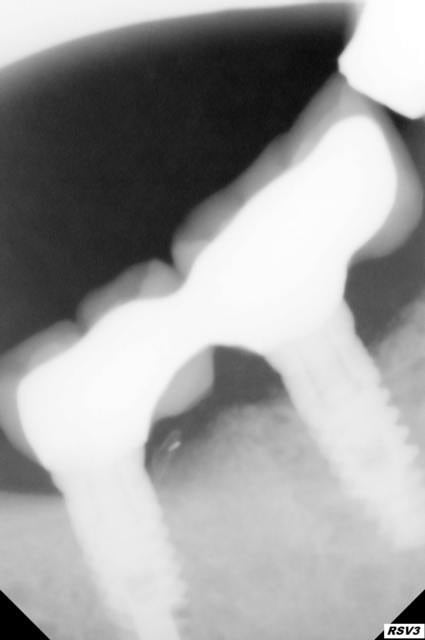

implants posés en mars 2015 patient fumeur 10 cig par jour, hygiene correcte

1 er radio le jour de la pose

2 e radio juillet 2015

3e radio fin décembre 2015

4é radio aujourd'hui soit 1 mois plus tard